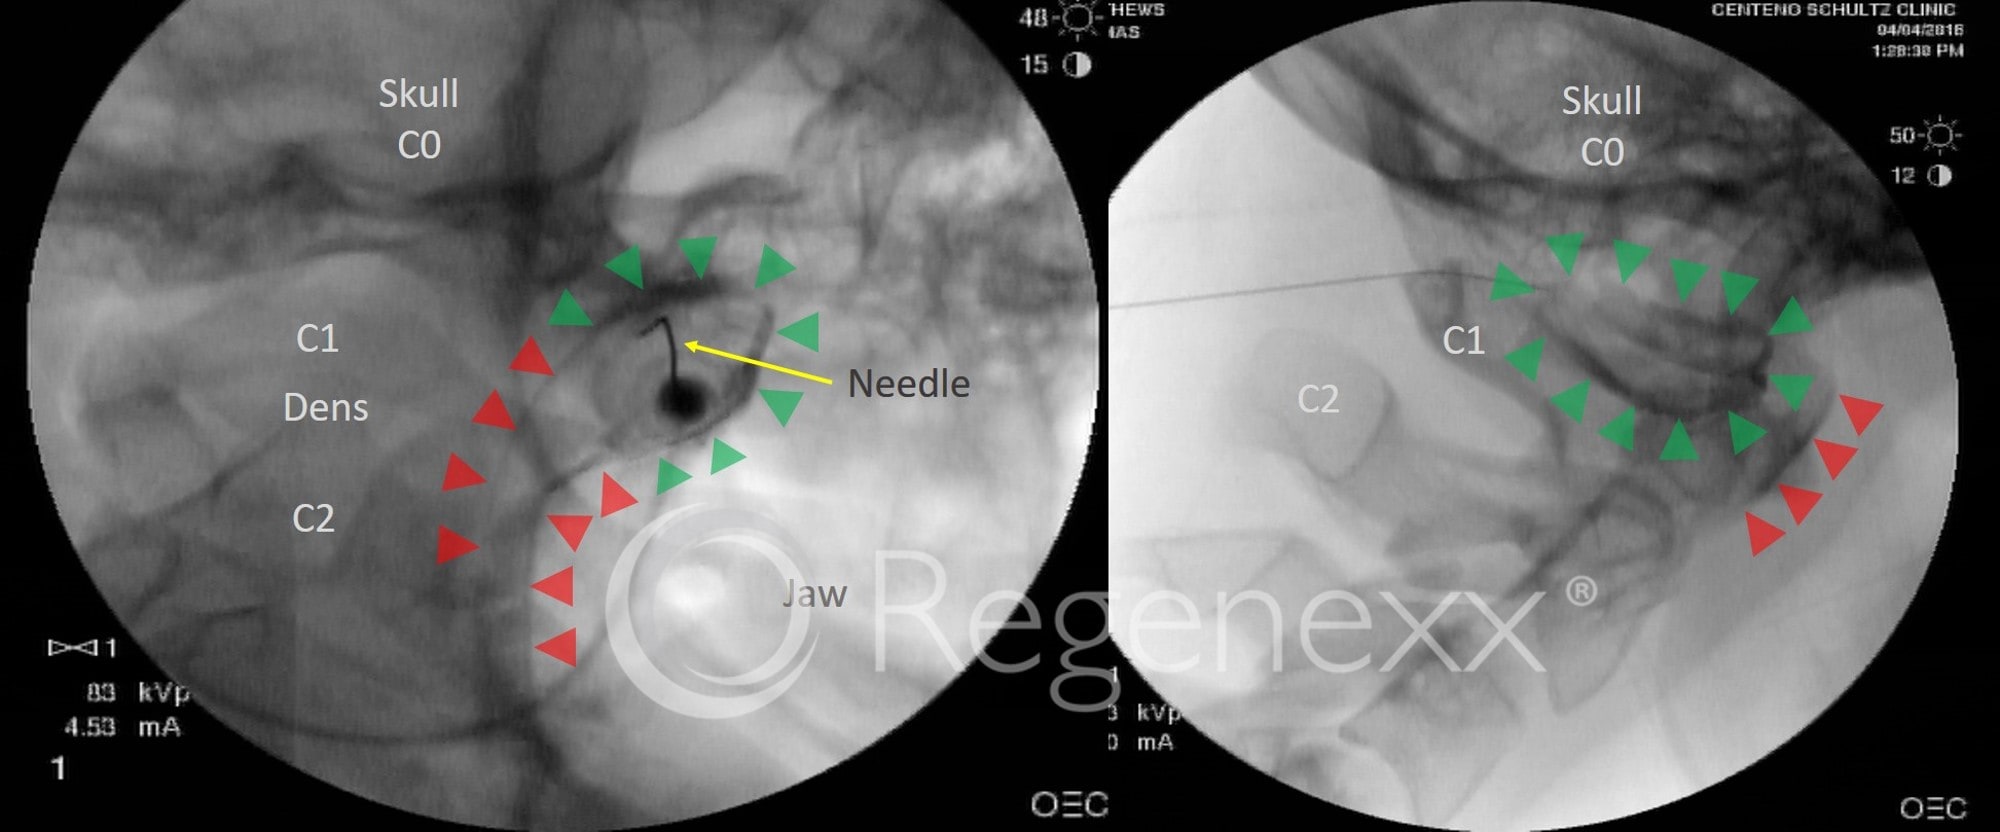

From regenexx.com

prolotherapy ccj instability keeping patients safe Prolo Surgery Prolotherapy involves injecting a dextrose or saline solution into an injury site to promote a healing response. Prolotherapy is an injection treatment used to relieve pain. It is a form of regenerative. The injection is intended to cause inflammation. Prolotherapy involves injecting a substance in or near the joint. The body responds to the. Your healthcare provider will inject a. Prolo Surgery.